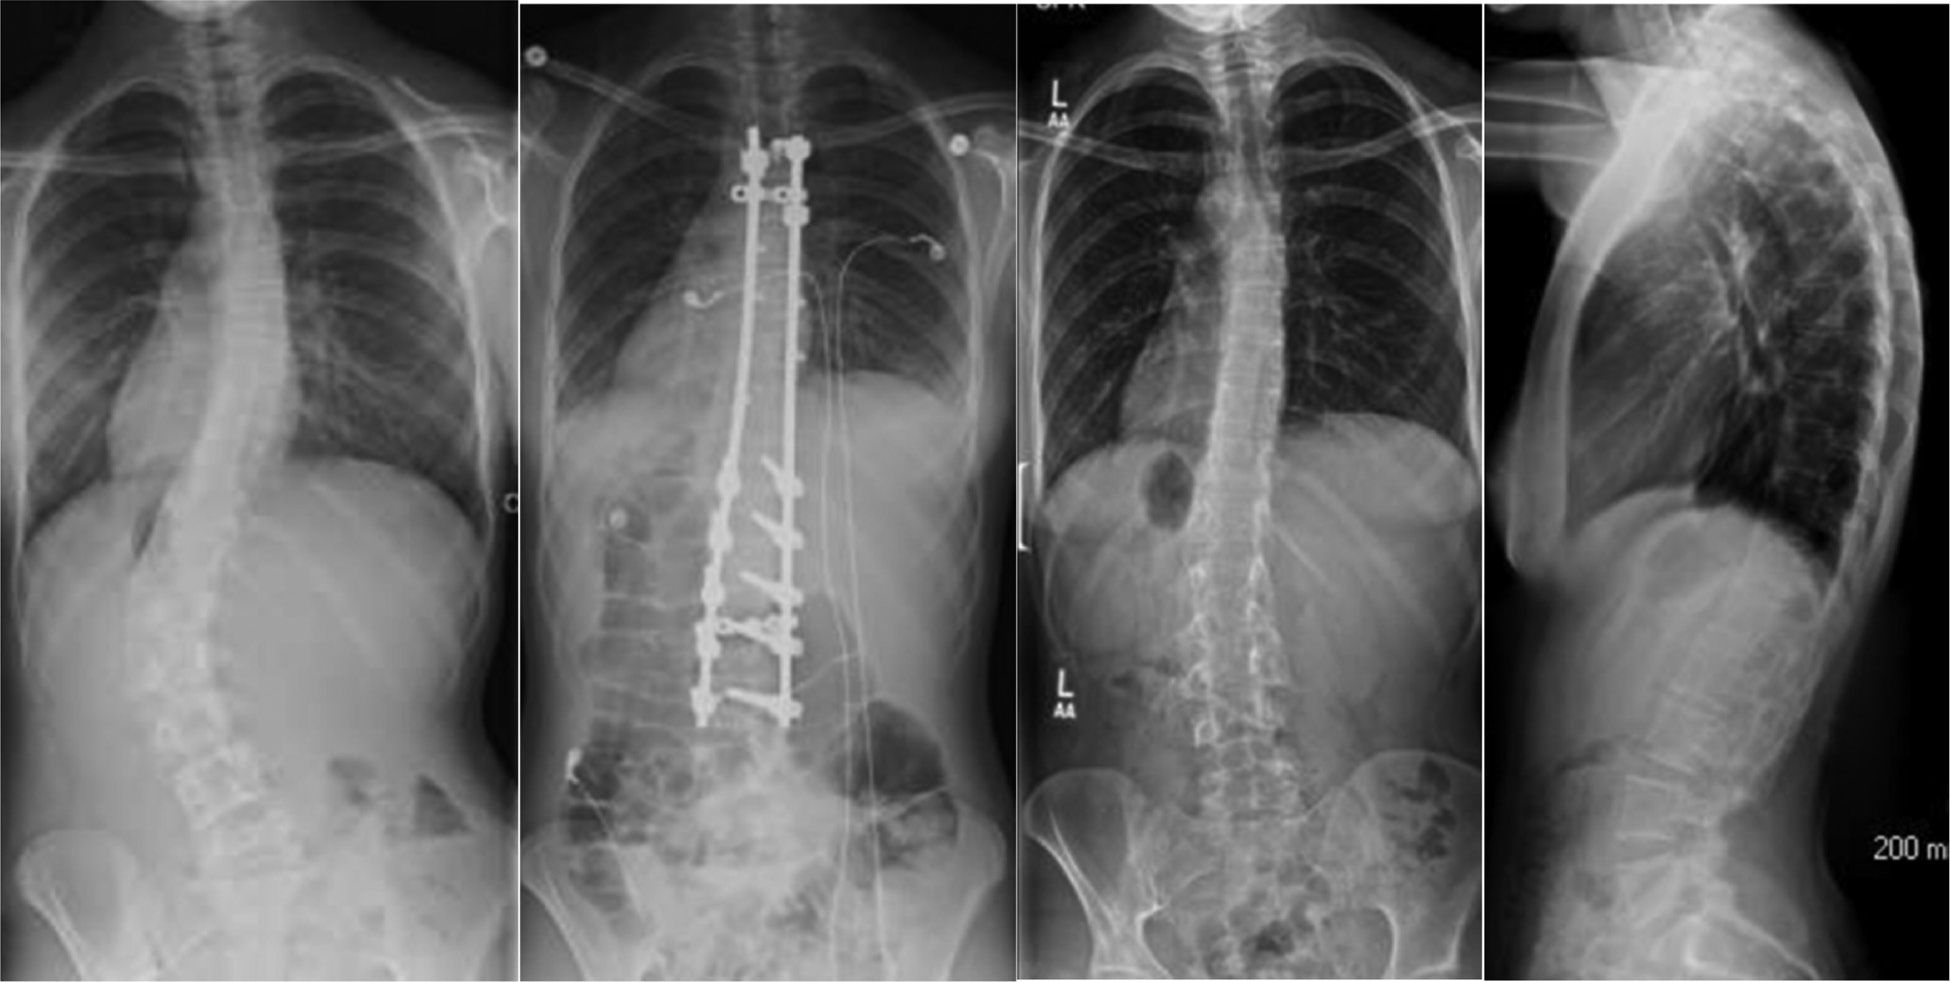

PJK is a sagittal plane deformity that can develop after spinal deformity correction. PJF has recently been defined as symptomatic PJK requiring revision surgery.25 Lee et al. defined PJK as ≥5 degrees kyphosis greater than normal from T2 to the most proximal level of instrumented fusion in patients with AIS.26 Although it is not uncommon for patients to develop radiographic evidence of PJK following PSF for AIS, the clinical significance of these findings does not always correlate with radiographs (Figure 4). Kim et al. found no significant differences in pain and self-image SRS subscores between patients who developed PJK and those who did not following PSF for AIS.27 Since there are multiple ways to define PJK, the prevalence in patients with AIS varies in the literature. Most reports suggest that anywhere from 9-46% of AIS patients who undergo PSF develop PJK.28

Figure 4. This female with AIS underwent PSF and developed painful PJK.

jposna20220030_fig4.jpg

For the patient who is at least a year from PSF and has unremitting pain with negative x-rays, blood work, and whose CT scan demonstrates solid fusion, we consider exploration, clinical assessment of bone union and possible implant removal. Shared decision-making is needed to take this step as some patients can continue to have pain and possible curve gradual curve progression (Figure 5).

Figure 5. This 14-year-old with AIS and a history of mild back pain and anxiety undergoes PSF for progressive AIS. She had persistent mid back pain for 5 years despite conservative management. Blood work and CT scan were negative for infection and implant or pseudarthrosis. At age 20 she undergoes implant removal and has had a decrease in her pain at most recent follow-up.

jposna20220030_fig5.jpg